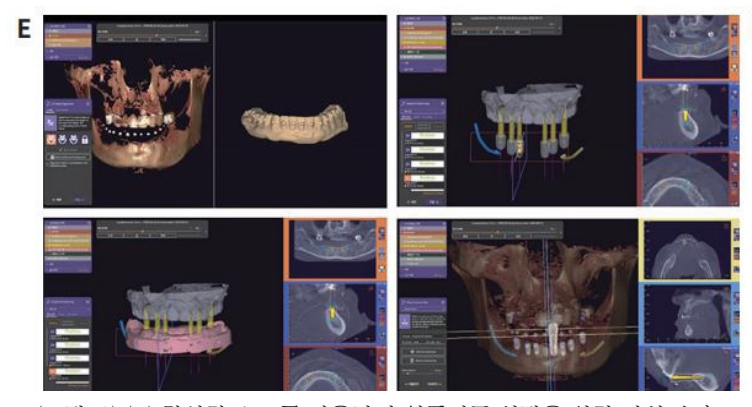

구강내 Scanning date Vertual wax-up date CT data를 융합하여 임플란트의 식립 위치, 방향을 결정하고 SurgiG uide를 제작하였다. SurgiGuide를 이용하여 임플란트를 식립하였으며, 1 주일 후에 stitch out 한 후 임시보철물을 위해 fixture에 scan body를 연결하고 seaming하여 PMMA 임시보철불을 제작하여 구강내에 장착하여 주었다.